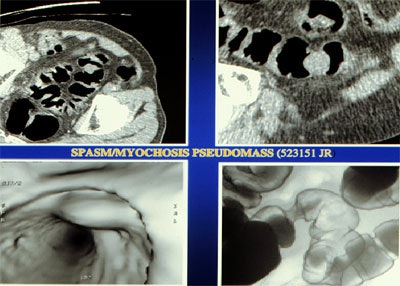

| Top left: Prone oblique CT scan of pelvis during virtual colonoscopy showing muscular thickening in sigmoid colon. Top right: multiplanar-reformatted image through muscle abnormality (myochosis) simulating a mass. Bottom left: Virtual colonoscopic view of "mass." Bottom right: double-contrast barium enema shows that "mass" is only spasm. Images courtesy of Dr. Marc Gollub. |

"Using anatomical and histological correlation, the true nature of (diverticular) disease has been well characterized and found to represent primarily a muscular disorder with resultant formation of diverticular outpouchings," Gollub and colleagues explained. "The muscular disorder is characterized by deposition of elastin in longitudinal muscle fibers (teniae coli), resulting in foreshortening of the colon. This causes a bunching up of the circular muscle fibers. No true hyperplasia or hypertrophy is found on histologic examination. This has been termed 'myochosis,' and is commonly referred to by the misnomer: 'circular muscle hypertrophy.'"

However, direct visualization of the colon wall can be disadvantageous in the setting of myochosis, where "the appearance may be confusing, and cause difficulty in distinguishing between myochosis, tumor, or underdistension in the sigmoid colon," they wrote. And the results from several published studies show that one-third to one-half of false-positives in VC may be attributable to diverticular disease.